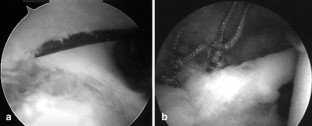

We evaluated an all arthroscopic technique for treating suprascapular nerve entrapment by cyst formation in the spinoglenoid notch. Eight patients showed positive MRI and EMG findings with clinical sign of weakness and pain and with atrophy of the muscle. All patients underwent an all-arthroscopic procedure. The patients were evaluated preoperatively and 6 weeks and 3 months postoperatively and for the latest follow-up by clinical examination, MRI, and EMG. All patients improved in terms of pain, strength, and function. We found six superior labrum anterior and posterior (SLAP) lesions. In these patients the cyst was drained, and the SLAP lesion was repaired. In two patients there was no communication between the joint and the cyst, and therefore capsulotomy was performed and left open. The results of our study show that arthroscopic decompression of the suprascapular nerve can be achieved by an all arthroscopic technique if the cyst formation is located at the spinoglenoid notch.

Fig. 1

Fig. 2